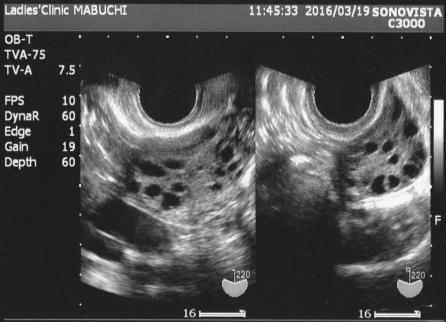

- 초음파 검사 : 질식 초음파를 통해 난소의 상태를 확인하고, 다낭성 난소의 소견을 관찰합니다. 생리 주기가 불규칙한 여성에서 자주 시행됩니다.